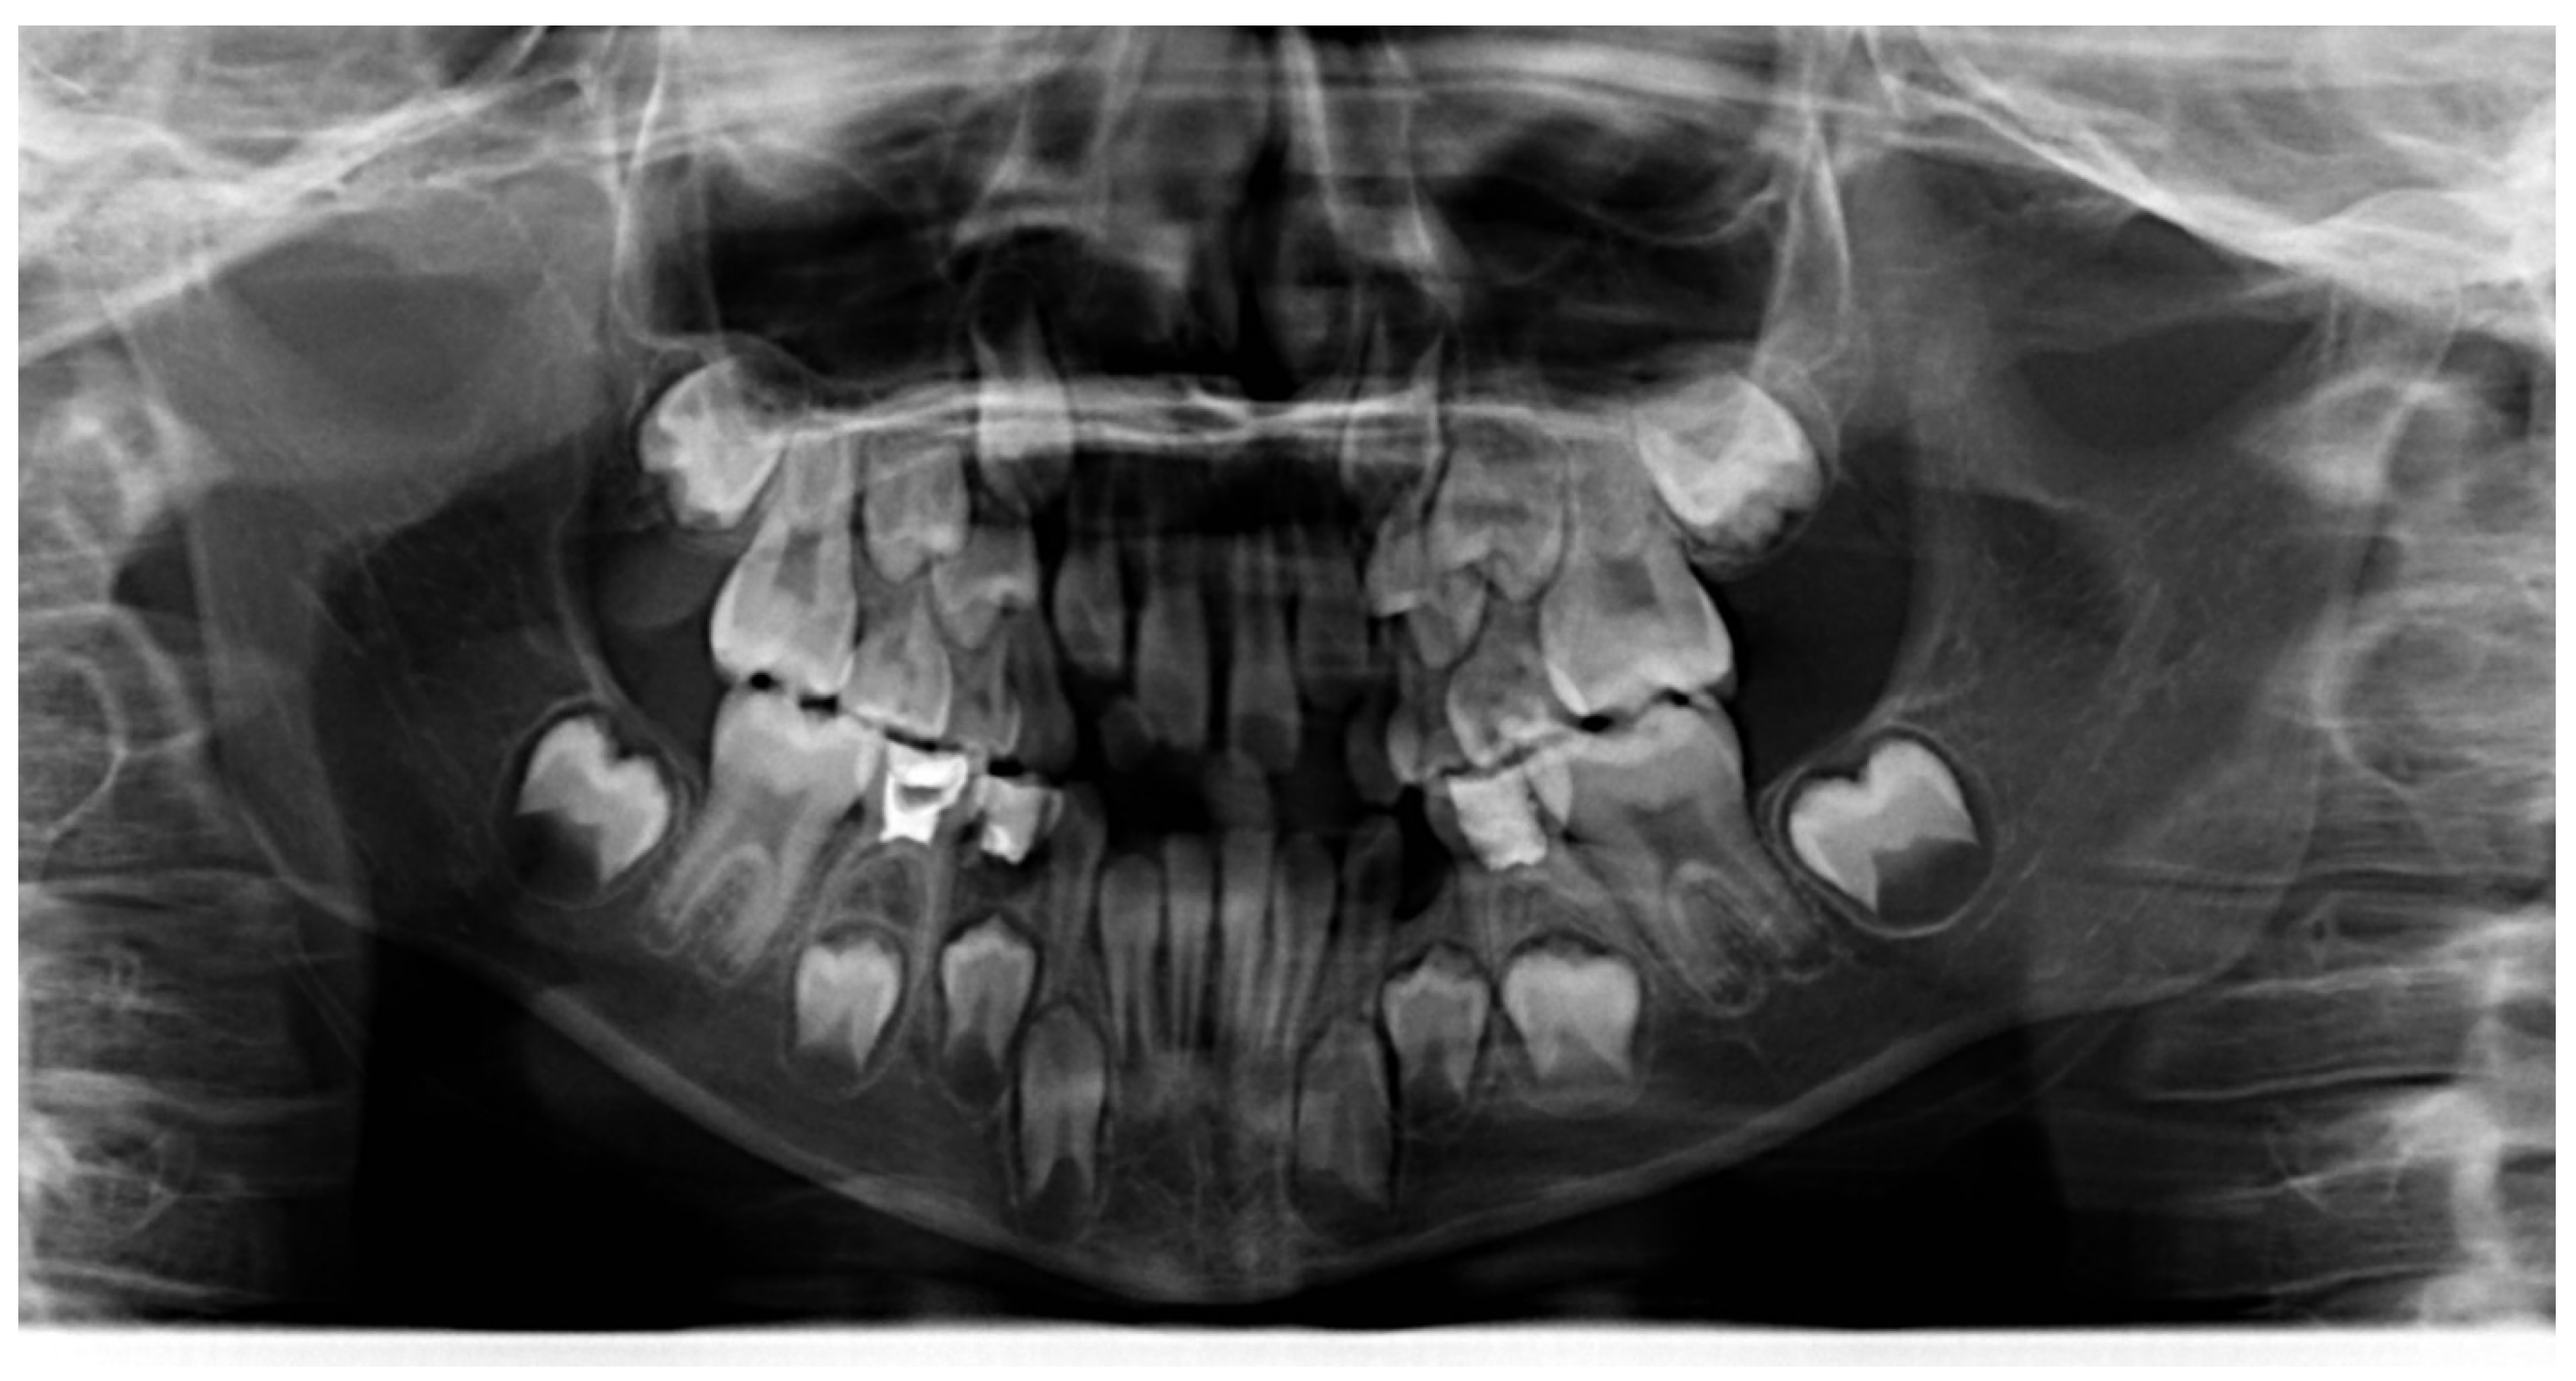

3.1. Clinical Case #1

| Cephalometric Analysis before Treatment | Val | Dev | Min | Med | Max | Diff |

|---|---|---|---|---|---|---|

| SNA | 74.5° | −xxx | 80° | 82° | 84° | 5.5° |

| SNB | 70.3° | −xxxx | 78° | 80° | 82° | 7.7° |

| ANB | 4.2° | x | 0° | 2° | 4° | 0.2° |

| sna-snp^Go-Gn | 30.7° | xx | 15° | 20° | 25° | 5.7° |

| S-N^sna-snp | 11.4° | N | 7° | 10° | 13° | 0° |

| S-N^PO | 25.2° | xxx | 11° | 14° | 17° | 8.2° |

| S-N^Go-Gn | 42.1° | xx | 27° | 32° | 37° | 5.1° |

| SNBa | 140.5° | xx | 124° | 129° | 134° | 6.5° |

| SND | 66.4° | −xxxx | 74° | 76° | 78° | 7.6° |

| IS^II | 120.3° | −x | 125° | 130° | 135° | 4.7° |

| IS:N-A | 1.9 | −xx | 3 | 4 | 5 | 1.1 |

| II:N-B | 2.2 | −x | 3 | 4 | 5 | 0.8 |

| II:A-Pog | 0.8 | N | −1 | 1 | 3 | 0 |

| Ls:Line S | 0.9 | N | −1 | 0 | 1 | 0 |

| Li:Line S | −0.8 | N | −1 | 0 | 1 | 0 |

| Cvm:S-Gn | −3.3 | −xxx | −1 | 0 | 1 | 2.3 |

| Mol Sup^P. Occl | 89.4° | N | 88° | 90° | 92° | 0° |

| N-S-Cop | 135.2° | xx | 117° | 122° | 127° | 8.2° |

| S-Cop-Go | 135° | −x | 137° | 143° | 149° | 2° |

| Cop-Go-Gn | 131.9° | xx | 115° | 120° | 125° | 6.9° |

| Cop-Go-N | 57.7° | xxx | 48° | 50° | 52° | 5.7° |

| N-Go-Gn | 74.2° | xx | 68° | 70° | 72° | 2.2° |

| II^Go-Gn | 94.3° | x | 92° | 93° | 94° | 0.3° |

| SOr:sna | 52.9 | 0 | 0 | 0 | 52.9 | |

| sna:Me | 57.3 | 0 | 0 | 0 | 57.3 | |

| S:N | 63.7 | −x | 66.6 | 69.6 | 72.6 | 2.9 |

| snp:A | 41.6 | 0 | 0 | 0 | 41.6 | |

| Go:Me | 57.7 | −xx | 66 | 71 | 76 | 8.3 |

| Wits | 0.1 | N | −2 | 0 | 2 | 0 |

| IS^N-S | 103.4° | N | 101° | 103° | 105° | 0° |

| Pog:N-B | 0.2 | 0 | 0 | 0 | 0.2 | |

| Pog:N-B—II:N-B | −2 | - | 0 | 0 | 0 | 2 |